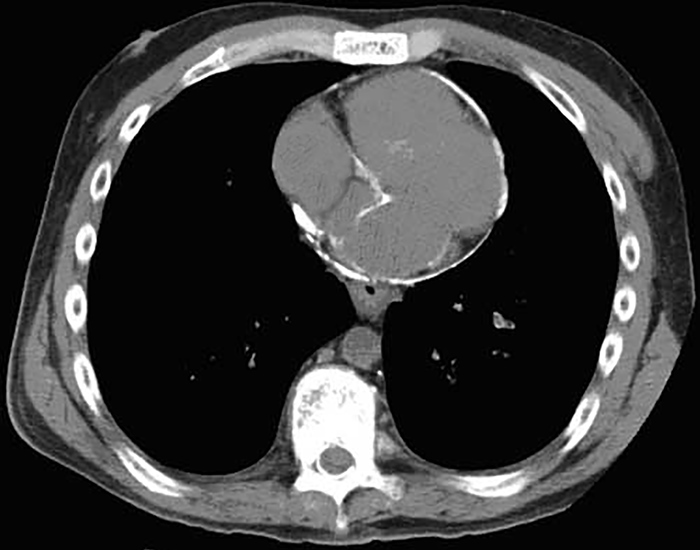

The patient is admitted to the hospital for further workup and treatment. After initial evaluation, a CT scan of the chest is obtained, an image of which is shown on the slide below.

Which of the following is the most likely diagnosis? A)Aortic dissection B)Constrictive pericarditis C)Hypertrophic cardiomyopathy D)Ischemic heart disease E)Viral myocarditis